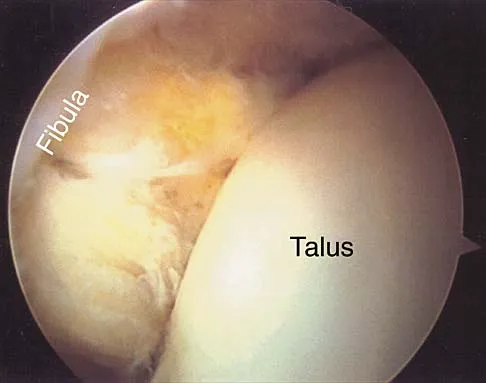

A 22-year-old professional ballet dancer reports a 3-month history of posterior ankle pain that occurs when she changes from a flat foot to pointe (hyperplantar flexed position). Examination does not elicit the pain with forced passive plantar flexion. A radiograph is shown in Figure 8. What is the most likely cause of the pain?

Options:

- Mild subtalar arthritis

- Posterior tibialis tendinitis

- Os trigonum entrapment syndrome

- Flexor hallucis longus tenosynovitis

- Retrocalcaneal bursitis

Correct Answer: Flexor hallucis longus tenosynovitis

Explanation:

The most common causes of posterior ankle pain in ballet dancers are flexor hallucis longus tenosynovitis and os trigonum syndrome. Flexor hallucis longus tenosynovitis differs from a symptomatic os trigonum by the absence of pain with forced plantar flexion and the presence of pain with resisted plantar flexion of the great toe. The pain is often felt in the posterior ankle and can be associated with a snapping or triggering sensation. Os trigonum syndrome commonly occurs in ballet dancers who perform in a position of extreme plantar flexion. The pain occurs from entrapment of the os trigonum between the posterior portion of the talus and calcaneus. Hamilton WG, Geppert MJ, Thompson FM: Pain in the posterior aspect of the ankle in dancers: Differential diagnosis and operative treatment. J Bone Joint Surg Am 1996;78:1491-1500.